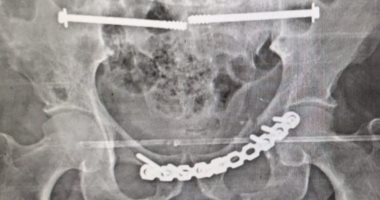

تشغيل وحدة جراحات كسور الحوض بمستشفى النيل فى شبرا.. ونجاح أول عملية جراحية أشعة

واستقبلت طوارئ المستشفى حالة طارئة، لرجل خمسيني يعاني من كسر في عظام الحوض نتيجة حادث سير، وبعد إجراء الإسعافات الأولية والفحوصات اللازمة، تقرر حجز المريض لإجراء الجراحة.

وأوضح الدكتور محمد عبد الغني، مدير المستشفى، أن الجراحة أجريت بنجاح على يد فريق طبي متميز، تحت إشراف الدكتور أحمد سمير، أستاذ جراحة العظام بكلية طب قصر العيني، والدكتور محمد فرحات، رئيس قسم جراحة العظام بالمستشفى، والدكتور أنور مصطفى، أستاذ التخدير بجامعة الأزهر.

شملت العملية تركيب شرائح ومسامير وتثبيت الحوض من الخلف بالفقرات العجزية باستخدام مسامير مجوفة.